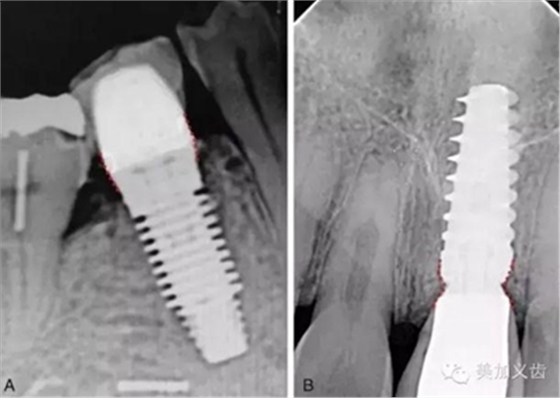

但根尖片是種植中必不可少的檢查,可以用來(lái)檢查基臺(tái)與種植體、修復(fù)體與基臺(tái)之間的密合程度,或者用于術(shù)后隨訪。

值得注意的是:使用根尖片來(lái)進(jìn)行術(shù)后隨訪,這是種植術(shù)后很重要的一件事情,而且需要定期來(lái)做,然后將拍攝出來(lái)的根尖片進(jìn)行對(duì)比,才能看到是否有骨吸收。但如果你每次拍攝的角度都不一樣,結(jié)果會(huì)讓你嚇一跳,怎么某段時(shí)間內(nèi)骨吸收這么多?!怎么某段時(shí)間骨頭又長(zhǎng)上來(lái)了?!太令人費(fèi)解了!

其實(shí)是你拍攝的角度不一樣,所得到的結(jié)果也不一樣,因此,采用平行透照技術(shù)就十分關(guān)鍵,否則你的術(shù)后回訪是沒(méi)有意義的。平行透照技術(shù)很簡(jiǎn)單,通過(guò)X線片定位器就可以做到,讓你的X線接收器和管球平行,這樣每次拍攝的角度都是一樣的了。